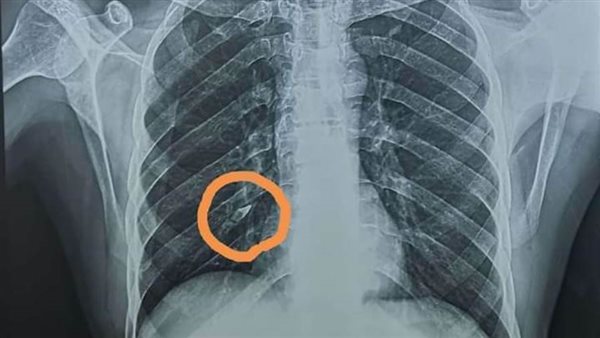

وقال الدكتور محمد الجزار مدرس جراحة القلب والصدر واستشاري مناظير الشعب الهوائية بطب بنها، أن المريض انتابته نوبة تشنجات نتيجة إصابته بمرض بالمخ أدى إلى غيابه عن الوعي فترة، وبعد تحسن حالته ونتيجة ضعف أسنانه وعمره المتقدم ومرض عينه تبين ابتلاعه "سنة من أسنانه" وتوقفها بالقصيبة الهوائية السفلي للفص السفلي من الرئة اليمني وتم تحويله من معهد الكبد بالمنوفية إلى قسم جراحة القلب والصدر ببنها الجامعي.